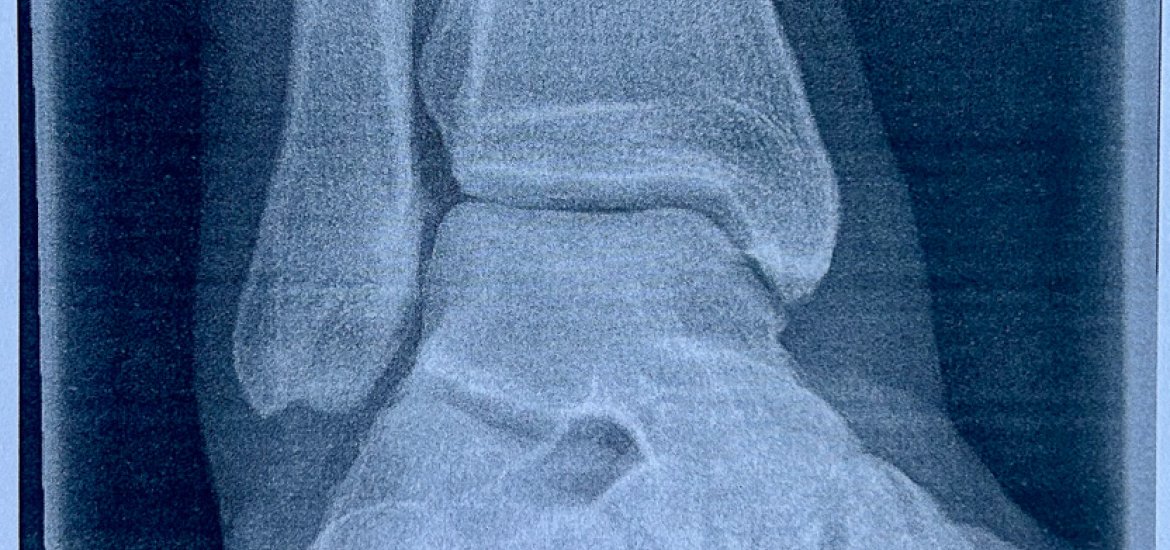

Am Dienstag bekam ich dann nach langem telefonieren und mit der Hilfe von der Sprechstundenhilfe vom Keinath einen MRT Termin für Mittwoch. Ich fuhr dazu mit dem Bike dann nach Giesing, MRT wurde fix gemacht, dann zum Keinath und leider bestätigte sich seine Vermutung. Mein Syndesmoseband ist durch. Fuck. Wie schlimm und was man jetzt macht sollten die Ärzte in der Schön Klinik in Harlaching entscheiden. Also weiter zur Schön Klinik in die Notaufnahme. Hier wartete ich dann geschlagene drei Stunden bis ich ran kam. Ich wurde auch nochmal geröngt und dann stand fest, jep durch und eine OP muss her. Oh shit. Gibts doch nicht. Trocken meinte die Ärztin, ein Termin für morgen wäre frei. Krass. Ok. Dann weiter gehumpelt zur Aufnahme. Alle Unterlagen unterschrieben, Blutabnahme und Anästhesie Gespräch durchgeführt. Nebenbei telefonierte ich mit Laura, die sich sofort von Sylt auf dem Weg runter machte und mit Orhan und sagte meinen Rasurtermin ab. Danach gings mit dem Taxi nach Hause und ich war in meinen Gedanken positiverweise nur im Hier und Jetzt. Ich betrachtete das nüchtern und meinte..ok, so muss es sein, also machen wir das so.

Am Donnerstag gings dann nüchtern um 8Uhr in die Klinik und ich bekam dort ein Zimmer zugewiesen. Zum Glück bekam ich noch einen Zimmernachbarn, der gerade seine OP mit der Entfernung der Schraube hinter sich hatte. Ebenfalls Syndesmoseband, aber so wie üblich beim Fußball zugezogen. Meine OP war zum Glück etwas anders. Ich bekam ein Thight Rope rein, welches zunächst mal ein Jahr drin bleibt. Gegen 13 Uhr kamen dann die Schwestern vorbei und meinten es ist soweit. Ich zog das schöne Überwurfhemd an und mit dem Rollstuhl gings bis zum OP. Einmal Übergabe an der Schleuse, dann auf die Liege und ab zur Anästhesie. Die Mädels dort waren richtig herzlich und kümmerten sich richtig gut um mich. Ich war schon etwas nervös und entsprechend hatte ich kalten Schweiß. Sie mussten daraufhin etwas lachen, weil ich mich mit einem Gleitschirm vom Berg stürzte und jetzt nervös war. Sind halt verschiedene Maßstäbe. Ich bekam zwei spritzen um meinen Beinnerv zu betäuben und tatsächlich fühlte ich langsam im gesamten rechten Bein nichts mehr. Ich wurde in den OP gebracht, zurecht gerückt und danach weiß ich nix mehr. Ich wachte dann im Aufwachraum auf, gefühlt eher wie nach einem normalen Schlaf und war bald voll bei mir. Mein rechtes Bein tat nicht weh, aber ich konnte es auch nicht bewegen. Ich wurde dann irgendwann raus gefahren zurück ins Zimmer und ich gab Laura kurz Bescheid. Sie kam dann auch gleich zu mir rein und so warteten wir dann bis ich vom Arzt frei gegeben wurde. Wären wir in der ersten Runde dabei gewesen wäre ich schon gegen 17Uhr raus. Also insgesamt hatte die OP mit Vorbereitung vielleicht 90 Minuten gedauert, reine OP Zeit wahrscheinlich nur 30 Minuten. Total krass. Am Abend sah ich dann auch noch die Anästhesie-Ärztin, sie versicherte sich, dass es mir gut geht und mit Laura gings dann am Abend zum Glück zurück nach Hause. Jetzt begann der spaßige Teil, der Geduldsteil.